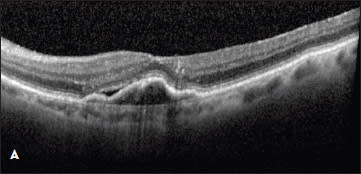

Figure 1. (top) A patient with a new occult CNV with PED and subretinal fluid was treated with two monthly intravitreal injections of ranibizumab with flattening of the PED and resolution of the SRF (bottom).

Case 1. This case involved a 92-year-old woman who presented with a new occult lesion in the left eye. Prior to her conversion, her baseline vision was 20/40. Despite new CNV with a PED and subretinal fluid noted on OCT, her vision remained unchanged (Figure 1). She was treated twice with intravitreal ranibizumab with dramatic resolution of the PED and subretinal fluid.